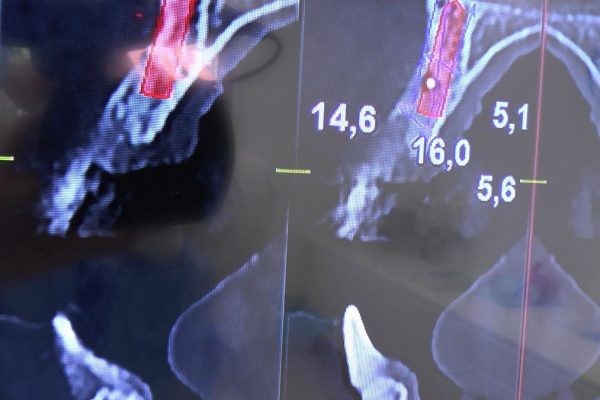

W ostatni weekend czerwca 2018 roku kursanci II Sezonu Preludium Implantologii odbyli piątą, finałową sesję, która w całości podporządkowana była praktyce. W ciągu dwóch dni zabiegowych Lekarze uczestniczący w szkoleniu przeprowadzili szereg zabiegów pod kierunkiem dr n.med. Violetty Szycik. Wszczepili 17 implantów oraz przeprowadzili ekstrakcje i zabiegi regeneracyjne kości. Zabiegi były wykonywane także w sedacji dożylnej z udziałem specjalisty anestezjologii i intensywnej terapii dr Jolanty Grzybowskiej. Preludium implantologii to nowy program edukacyjny dla adeptów implantologii stomatologicznej, którego celem jest wprowadzenie do implantologii poprzez pozyskanie wiedzy w szerokim zakresie i uwzględnieniem szczegółów mających decydujące znaczenie dla powodzenia leczenia implantologicznego. Ale tak jak wszystkie szkolenia w Instytucie Vivadental, w tym wiodące Practiculum Implantologii, zorientowane jest na praktyce i samodzielnym wykonywaniu zabiegów pod kierunkiem Mentora. To najlepsza edukacja w medycynie zabiegowej, a zarazem najlepszy start do implantologii.